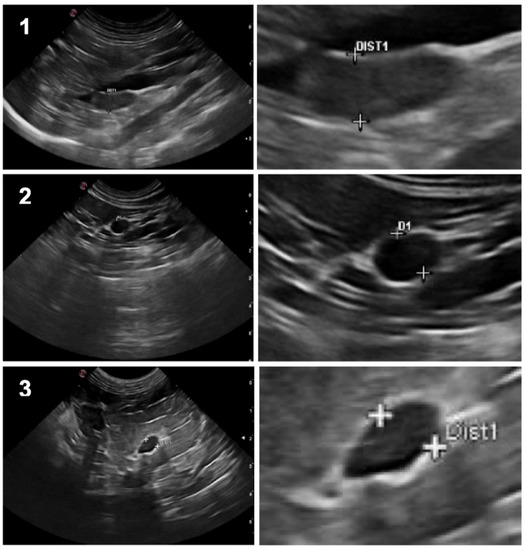

| Dimension (mm) 1 | - | 5.5 ± 0.8 (4.0–7.9) | 5.1 ± 0.9 (3.1–7.8) | 0.005 |

| Limits | Regular | 52 (81%) | 55 (86%) | 0.629 |

| Irregular | 12 (19%) | 9 (14%) | ||

| Shape | Oval | 41 (64%) | 20 (31%) | 0.005 |

| Bipolar | 17 (27%) | 26 (41%) | ||

| Fusiform | 6 (9%) | 18 (28%) | ||

| Cortico-medullary differentiation | Without | 50 (78%) | 54 (84%) | 0.344 |

| With | 14 (22%) | 10 (16%) | ||

| Echogenicity | Hypoechogenic | 26 (41%) | 33 (52%) | 0.186 |

| Mixed | 31 (48%) | 25 (39%) | ||

| Hyperechogenic | 7 (11%) | 6 (9%) | ||

| Echotexture | Homogeneous | 40 (63%) | 42 (66%) | 0.804 |

| Heterogeneous | 24 (38%) | 22 (34%) | ||

| Hyperechogenic foci | Present | 9 (14%) | 5 (8%) | 0.289 |

| Absent | 55 (86%) | 59 (92%) | ||

| Focal lesions | Present | 3 (5%) | 1 (2%) | 0.500 |

| Absent | 61 (95%) | 63 (98%) |